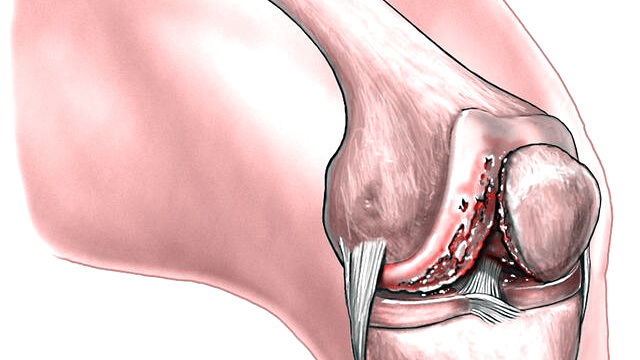

为什么会得关节炎?这和不同的关节炎的不同发病机制有关。关节炎按照病理生理学分类,可以分为两大类:(1)非炎症性关节炎:退化性关节炎和创伤性关节炎a) 退化性关节炎:通常情况下,是最常见的关节炎,也是我们口中常说的“关节炎”,大部分是老人家得,起因是关节软骨的退化,也就是关节磨损了,老化了,因此也叫“老年性关节炎”。b) 创伤性关节炎:因为关节受过外伤,导致关节内结构损伤,迁延不愈,逐渐加重,形成关节炎性改变,跟年龄关系不大,老人和年轻人都会得。